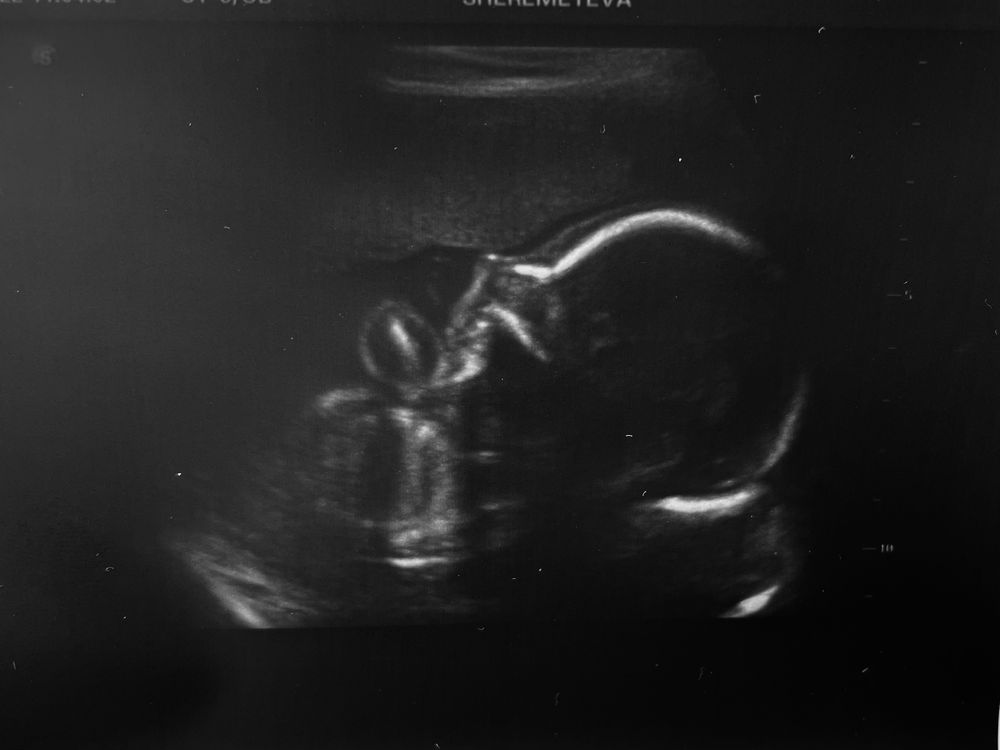

Второй скрининг ✔️

Обожаю детские носики!!!! Они прекрассны🥰🥰🥰 Сколько весит красотка? А мне на первом переставили на 9е марта,а в этот раз ничего не сказали(

Алена, весит 399гр, как-то многовато… Так и оставили может 9 число)